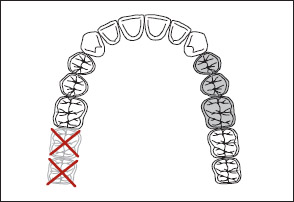

7. The extent of the modification is not considered, only the number of additional edentulous areas (Fig 1-28).

Fig 1-28 The extent of the modification is not considered; only the number of additional edentulous areas is important. Consequently, both illustrations represent Kennedy Class II, Modification 1 arches.